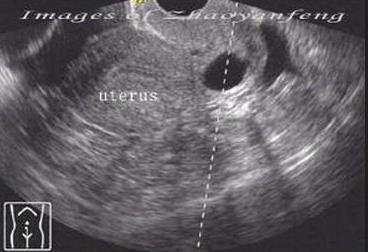

门诊经常能碰到病人拿着B超单来咨询,“医生,我子宫上面长囊肿了,要不要紧,该怎么治疗?”不用看单子就知道,肯定是宫颈纳囊。其实,只要在B超室待上半天,你就会发现大部分女性都有宫颈纳囊。这么常见的纳囊到底是什么东西呢,对我们的健康有什么影响,需要治疗么?下面我就来说说宫颈纳囊。

宫颈纳囊就是宫颈纳氏囊肿的简称(英文为Nabothian cyst),又称为宫颈潴留性囊肿或宫颈腺囊肿。德国解剖学家Martin Naboth早在1707年就在文章中描述了这种特殊的囊肿,纳氏囊肿也正是用他的名字来命名的。

宫颈表面存在着鳞状上皮与柱状上皮,周边为光滑的鳞状上皮,而中央为柱状上皮,肉眼看上去就像糜烂,就是大家俗称的“宫颈糜烂”。但其实这只是一种正常的生理现象,是不需要治疗的,糜烂面的大小受体内雌激素的影响。柱状上皮与鳞状上皮也存在着动态变化,柱状上皮可脱落而被鳞状上皮取代。当柱状上皮尚未脱落,仍可分泌黏液,但其周围已被鳞状上皮包绕,于是就形成了一个腺开口,这就类似于我们脸上的毛孔。然而鳞状上皮生长迅速,新生的鳞状上皮可将腺管开口覆盖或伸入腺管内,闭合了腺管开口,使内部分泌的黏液不能排出,就类似于脸上的毛孔被堵塞。黏液逐渐积聚,同时腺管周围结缔组织增生,压迫腺管口,于是就形成了一个突起的灰白色或黄色的潴留性囊肿,也就成了宫颈上的一粒“青春痘”。

宫颈纳囊通常较小且没有明显症状,可自行消退,即使持续存在,对女性健康是没有影响的,也不会影响生育,一般是不需要治疗的。但我们也遇到过宫颈纳囊长到3cm的,或者引起不适症状,这些情况也可以考虑对纳囊进行处理。治疗方法主要有电灼、激光等,但这也就类似于将青春痘挤出来,一段时间后有可能再长出新的纳囊,其实如果没有症状也不用急着去治疗。